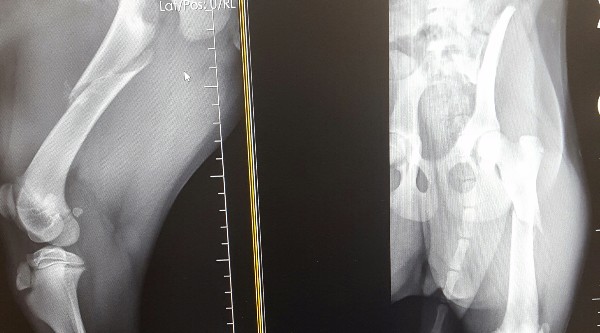

This is Holly, a roughly 4 month old Lab mix. Unfortunately, Holly has a broken femur and her previous owners were unable to continue caring for her. She was surrendered on Christmas Day. Since then, this sweet little bundle of cuteness has brightened the life of every person to come in contact with her. Despite the immense pain she feels, she continues to be the happiest and most loving dog I've ever seen. I'm asking for help with her surgery because she really deserves the highest standard of care available and shouldn't have to live one more day with that broken leg. Rehab will be tough and it will be long but with her wonderful attitude, she should make a complete recovery. Money raised will go towards surgery and follow-up visit costs.